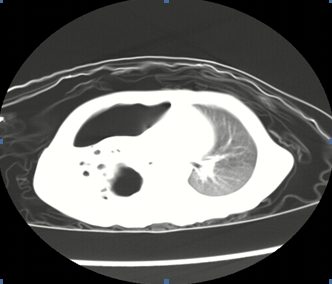

1、壞死性肺炎定義?壞死性肺炎是侵襲性肺炎的并發(fā)癥,其特征為實變區(qū)域內(nèi)出現(xiàn)壞死病灶;2、壞死性肺炎的常見病原體?細菌、支原體、真菌、結核桿菌、病毒(H1N1流感病毒);3、兒童壞死性肺炎的病因有哪些?1)肺炎鏈球菌壞死性肺炎:肺炎鏈球菌引起的壞死性肺炎并胸腔積液增多,多數(shù)為3歲以下嬰幼兒,表現(xiàn)為高熱、咳嗽,肺部有固定性濕性羅音,初期胸片或CT表現(xiàn)為大葉肺實變,約在1-2周肺實變區(qū)出現(xiàn)多發(fā)的小空洞并膿胸,炎性指標如外周血WBC和N↑↑,CRP常>100mg/L,痰液、胸水肺炎鏈球菌培養(yǎng)陽性,一些病例血培養(yǎng)陽性,胸水檢查為膿胸表現(xiàn),后期有肺大泡或氣胸,一些發(fā)生支氣管胸膜瘺;2)金黃色葡萄球菌壞死性肺炎(SA-NP):發(fā)熱、呼吸窘迫、有膿痰、可咯血、病情重、可進展迅速、伴發(fā)休克常見,病死率較高、白細胞降低(PVL殺白細胞素-陽性的SA)、易于合并其他部位的感染(皮膚、軟組織等);3)CA-MRSA:突出表現(xiàn)為皮膚和軟組織感染,多位于上下肢,共同特征為多部位受累,包括肺炎伴膿胸、骨髓炎、關節(jié)炎、皮膚、心內(nèi)膜炎,可有爆發(fā)性紫癜,死亡和PVL產(chǎn)生有關,發(fā)生于健康的青少年和學生,前期可有肢體疼痛,迅速出現(xiàn)高熱、咳嗽,因病理表現(xiàn)為急進性出血壞死性肺炎,可出現(xiàn)痰中帶血或咯血,同時出現(xiàn)膿毒血癥表現(xiàn)如明顯中毒癥狀,呼吸增快、心率增快,C反應蛋白增高,因PVL產(chǎn)生,白細胞可減少。影像學表現(xiàn)為多葉肺泡浸潤或高密度實變,迅速出現(xiàn)空腔和膿胸或膿氣胸;4)化膿性鏈球菌:臨床表現(xiàn)為皮疹、脫皮,壞死性肺炎并胸腔積液,鏈球菌感染中毒休克綜合征,耐藥報道少;5)難治性肺炎支原體:(1)病情重:合理大環(huán)內(nèi)酯類抗生素治療后仍持續(xù)高熱、劇烈咳嗽;(2)雙側或單側大葉肺實變,合并少-中量胸腔積液;(3)易合并肺外表現(xiàn);?(4)炎性指標升高:中性粒細胞、血沉和CRP升高,血凝指標也升高;??(5)患兒病情重(除肺部嚴重病變外尚可有多系統(tǒng)肺外損害);?(6)遷延不愈者(病程常大于4周)遺留肺部后遺癥;6)侵襲性肺曲霉?。簤乃佬苑窝??有基礎肺疾病和原發(fā)免疫功能障礙,靠近胸膜結節(jié)實變,有空洞形成,伴胸膜受累;7)干酪性肺炎:原發(fā)性肺結核惡化,可多發(fā)空洞,可有支氣管播散。